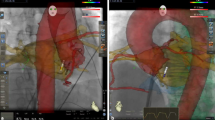

Incorporating preprocedural CT or MRI to an EAM can further assist with identification of channels. One approach that implements automated detection of arrhythmogenic substrates (ADASs) defines areas of dense scars with border zone corridors that may act as channels for VT. Preliminary studies using this software are promising [31], but prospective validation is awaited. Note that simple manipulaton of voltage windows on a traditional EAM voltage map alone can display channels that can correspond to ADAS acquired data (Fig. 5).

Voltage mapping with and without ADAS in a 72-year-old male with previous anteroseptal infarct: A voltage mapping using traditional range of 0.5–1.5 mV shows a large area of scar core over the antero-septum with no definite channel. Adjusting the voltage window to 0.1–1.0 mV reveals a channel between two areas of dense scar. B Pre-procedural cardiac CT with automated detection of arrhythmogenic substrate (ADAS). C Activation map of clinical VT, demonstrating conduction through the conducting channel identified with both ADAS and voltage mapping. (Used with permission from Dr. Geoffrey Lee, from [31]).